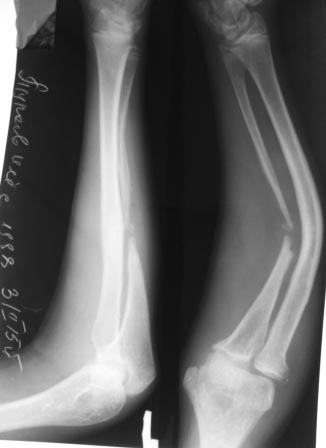

Уважаемые коллеги. Обратился мальчик 1998г.р. с жалобами на деформации предплечья. Со слов матери 2008г оперирован мною по поводу перелома обеих костей предплечья. и/м остеосинтез спицами ( с 2010года перешли на пластины-DCP,LCP).через 2 месяца после заживления спицы удалены, я сам не помню. И через 7 лет явились с претензиями что со слов больших докторов из центра неправильно оперирован и якобы спицы удалены раньше срока и поэтому развился такая деформация. Я не понял, почему развилась такая атрофия и дефект локтевой кости, ведь по представленным снимкам п/о и через 2 месяца все было нормально... или родители чего-то скрывают..Функция локтевого и луче-запястного суставов сохранены, имеется небольшое ограничения супинации и пронации. Я обещал родителям, что выложу на форуме, и совместно с опытными специалистами подумаем.В плане корригирующая остеотомия лучевой кости, резекция концов ложного сустава локтевой кости . аутотграфт из половины окружности малоберцовой кости достаточной длины, остеосинтез методом Илизарова. Уважаемые коллеги , жду и надеюсь на Ваши рекомендации.. С уважением Абдурашид.

Добрый день, уважаемые коллеги. По моему вы недостаточно серьезно оцениваете имеющуюся ситуацию. При первом взгляде на рентгенограммы возникает только одна аналогия - латентный ложный сустав костей голени. Тот же дефект малоберцововй кости, та же дугообразная деформация большеберцовой кости. Можно лишь гадать о том, что послужило пусковым механизмом развития такой деформации костей предплечья, но сейчас вы имеете дело с явным нейротрофическим нарушением на данном сегменте.

И если это так (невролог, ЭМГ, ЭНМГ), то простого решения этой проблемы нет.

И вам придется давать ответы на несколько вопросов. Возможно ли без укорочения исправить угловую деформацию лучевой кости. Как надежно заместить дефект локтевой кости. Здесь уже нельзя говорить о ложном суставе, поскольку после исправления деформации предплечья диастаз между фрагментами увеличится. Предлагаемый метод пластики вызывает большие сомнения, поскольку имеются явные трофические нарушения дистального фрагмента локтевой кости. Наиболее надежна в этом случае микрохирургическая аутотрансплантация малоберцовой кости.

Уважаемые доктора, рассуждать сейчас о причиных деформации предплечья и формирования дефекта локтевой кости достаточно сложно. Вероятно сама травма и последующие вмешательства привели к выраженному нарушению васкуляризации диафиза локтевой кости. Атрофия мышц предплечья связана с локальными нейро-трофическими изменениями на уровне проксимальной/3 предплечья.Для исправления подобных деформаций в нашем институте травматологии применяются корригирующие остеотомии лучевой кости с одновременной пластикой дефекта локтевой кости сегментом малоберцовой кости на микроанастомозах, с обязательной ревизией сосудисто-нервных пучков.